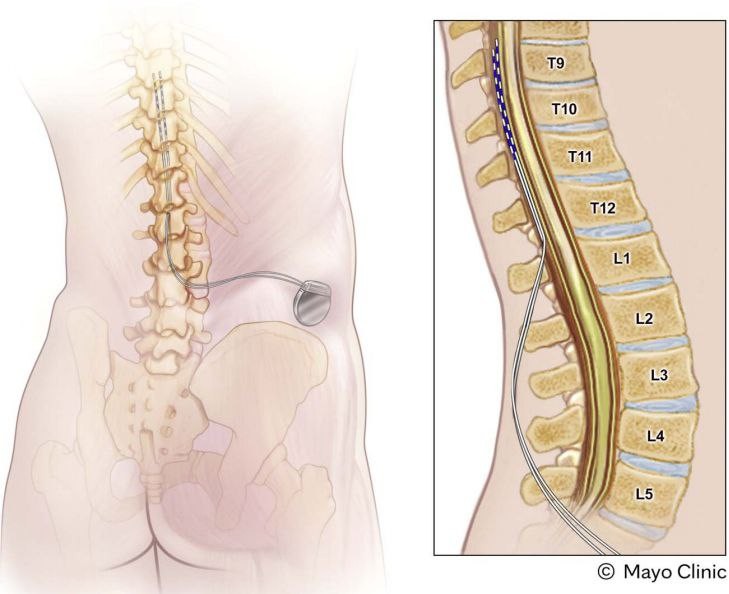

脊髓电刺激(spinal cord stimulation, SCS)

项目类型

器械质押区

起投金额

250000USDT

每日释放:0.95

释放周期:89 天

已购: 320

剩余: 0

Inceptiv

项目类型

器械质押区

起投金额

5500USDT

每日释放:0.8

释放周期:130 天

已购: 17818

剩余: 0

AI闭环植入式可充电脊髓电刺激系统 NewStim

项目类型

器械质押区

起投金额

50000USDT

每日释放:0.95

释放周期:100 天

已购: 3000

剩余: 0